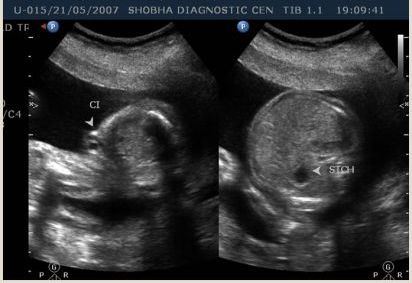

Routine Sonography

To know growth and general condition of the baby.